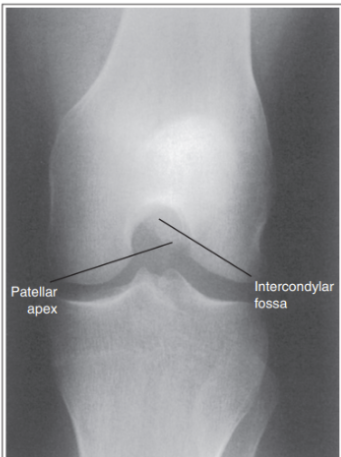

What are the issues with this AP knee?

Intercondylar fossa is shown

Knee is flexed and not straight